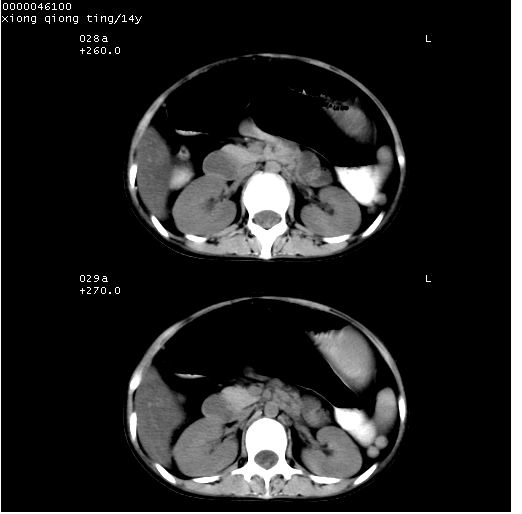

患儿 女,14岁。不规则发热一周,偶感头痛,无抽搐及呕吐。pe:神清,精神差,双侧瞳孔等大等圆,对光反射敏感,双肺未闻及明显啰音,心音有力,腹部触之似揉面感,下腹压痛,无反跳痛。

腹部b超提示:子宫缩小,盆腔积液,肝实质回声密集。

临床诊断:发热原因待查:1)腹部结核感染。2)伤寒?3)结缔组织病?

中下腹及盆腔ct轴位平扫+增强扫描(层厚10mm,螺距1.0,重建间隔10mm),图像如下:

(注:患儿检查当日上午9时口服胃肠道对比剂,下午3时许行ct扫描检查,未行对比剂直肠保留灌肠,检查当日患儿腹泻)

中下腹及盆腔ct轴位扫描(ps+ce)提示:腹部肠管明显充气扩张,并见数个不同宽度之气液平面;疑不全性肠梗阻或肠郁张。临床会诊考虑为患儿腹泻,肠郁张所致;后来未经特殊处理,患儿大便恢复正常,亦无腹胀。

临床出院诊断:1)结核性腹膜炎。2)腹膜后淋巴结结核。3)脂肪肝。